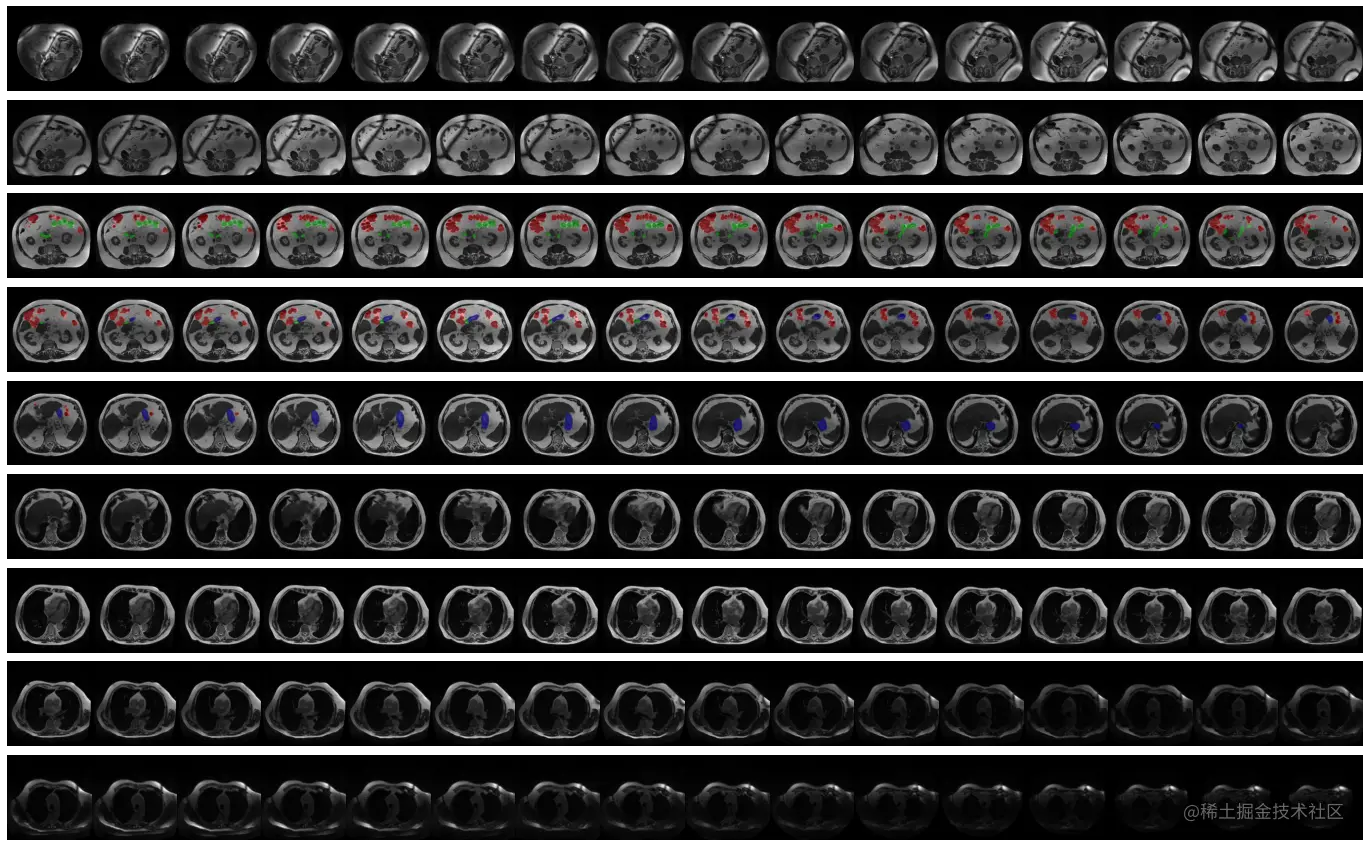

DEMO_CASE = 134

print(f"\n\n... PLOTTING DEMO CASE ID #{DEMO_CASE} ...\n\n")

plot_case(DEMO_CASE)

DEMO_CASE = 9

print(f"\n\n\n\n... PLOTTING DEMO CASE ID #{DEMO_CASE} ...\n\n")

DEMO_CASE = 7

DEMO_DAYS = [01319]

for _dday in DEMO_DAYS:

print(f"\n\n\n... PLOTTING DEMO CASE ID #{DEMO_CASE} - FOR DAY #{_dday} ...\n\n")

plot_case(DEMO_CASE, day=_dday)